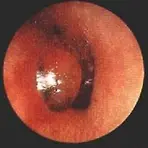

이비인후과의 진료중 중이염의 진단은 많은 부분을 차지하고 있는 질병중 하나입니다. 또한 중이염은 성인들보다는 어린아이들에게 많이 발병을 하며 중이염이 만성적으로 번지게 되면 청력약화 및 일상 생활중에도 귀에 물이 들어가지 않게 각별히 신경을 써야 하는등 생활속에서도 많은 불편함을 안겨주는대요. 비교적 성인 남녀보다는 어린아이들은 면역력이 비교적약하고 이로 인하여 건강에 위협을 많이 받습니다. 귀가 청력을 잃는 다면 생활은 필수불가결적으로 매우 불편할것이고, 많은 어려움이 있습니다. 중이염의 원인과 증상등을 알아보도록 하여 귀의 건강을 미리미리 챙겨보도록 하세요! #중이염 원인중이염 원인은 중이염은 중이강 내에 일어나는 모든 염증성 변화를 총칭하는 것으로 중이강, 중이점막 상피세포 및 상피하 조직의 변화와..